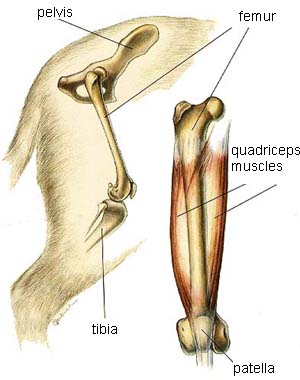

The musculoskeletal system includes all the muscles, bones and joints.

- Rear Leg

Rear Leg